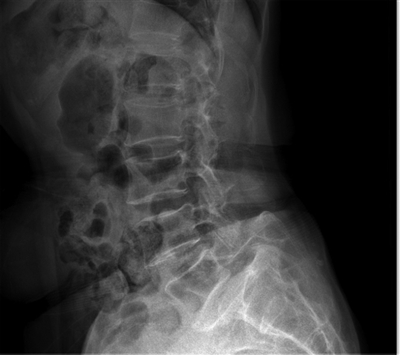

腰5椎体向前滑脱,继发性椎管狭窄。

经过检查,胡奶奶病情复杂,其长期腰痛与腰5椎体峡部裂导致椎体滑脱、椎管狭窄相关。近期剧烈的左下肢疼痛,是由腰2/3椎间盘左侧突出并压迫左侧腰3神经根所致,要想从根本上解决问题必须实施两处手术。但这次手术真正的挑战在于胡奶奶年岁高,营养状况差,仅仅只有32公斤,体重甚至不如一个儿童。同时,胡奶奶尚有贫血与骨质疏松,无论是对麻醉还是手术的耐受都极差,普通手术量的失血以及手术时间对于胡奶奶而言可能都是巨大的风险。而较差的身体条件也可能导致后期伤口的愈合不良,甚至继发感染等,“牵一发而动全身”。